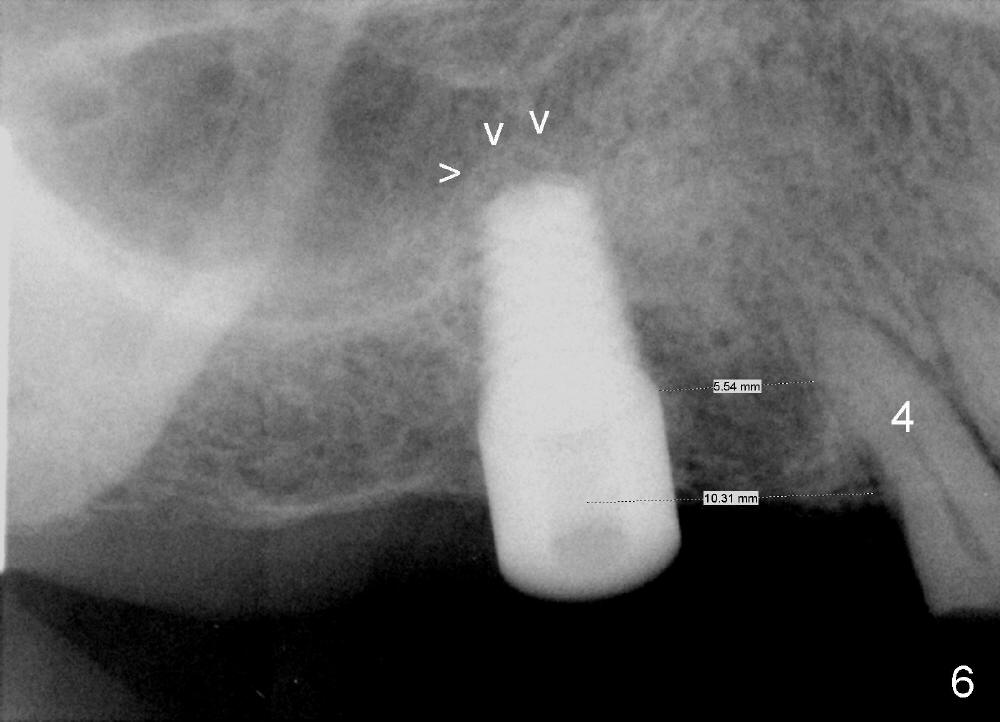

The pilot drill is easily penetrating the cancellous bone, suggesting low bone density. The remaining osteotomy is finished by bone expanders (Fig.4: 4.3 mm) and taps until 6x14 mm at gingival level. There is no sinus perforation when the 6x14 mm tap is removed from the osteotomy (Fig.5). Sinus lift is observed (Fig.6 arrowheads) when a 6x14 mm implant is placed with insertion toruqe > 60 Ncm. The distance to the adjacent tooth remains consistent to that of design.